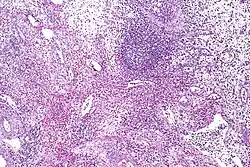

| Eosinophilic cystitis showing edematous and chronically inflamed lamina propria with numerous eosinophils. | |

Cystoscopy typically reveals large mucosal edema along with erythematous, polypoid, velvety red lesions. It can be mistaken for vesical rhabdomyosarcoma in children.[25] Eosinophilic cystitis is hard to differentiate from other cystitis types (like interstitial and tuberculous cystitis), neoplastic lesions (like carcinoma in situ), and other bladder cancers. Therefore, in order to confirm the diagnosis of eosinophilic cystitis, biopsies are required.[2] Transmural inflammation is present histologically, primarily with eosinophils. The lamina propria has more severe edema and inflammation. A contracted bladder may result from focal muscle necrosis and varying degrees of detrusor muscle fibrosis.[26]